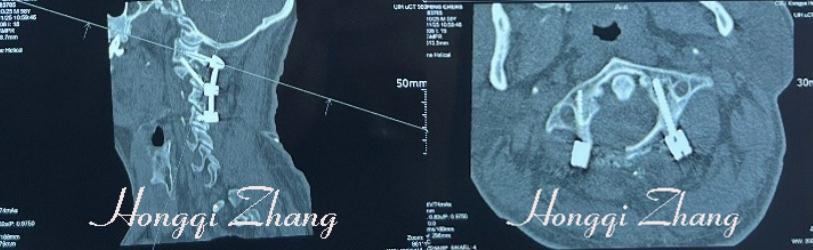

他例举了58岁的毛先生的案例。毛先生因颈部活动受限1年入院,检查显示由于脊索瘤,导致右侧环椎后弓破坏、椎动脉被肿瘤浸润包裹。按传统方法,在手术清除肿瘤后,一般会做枕颈融合来维持局部的稳定性。

而张宏其教授团队在刮除病灶后,采用单纯后路病灶清除、左侧环椎椎弓根+无导针引导的徒手Magerl技术,右侧单用环椎椎弓根钉,及C3、4钉棒固定,再植骨。

完美解决了不能用钛缆加强后柱稳定性的缺陷,完整保留了环枕关节,即保留了患者的枕颈部的大部分屈伸功能和点头动作的功能,大大改善了术后患者的生活质量。术后一周毛先生就可行走自如。

▲术后X片、CT示:病灶清除满意,内环枢椎“△”内固定位置满意。